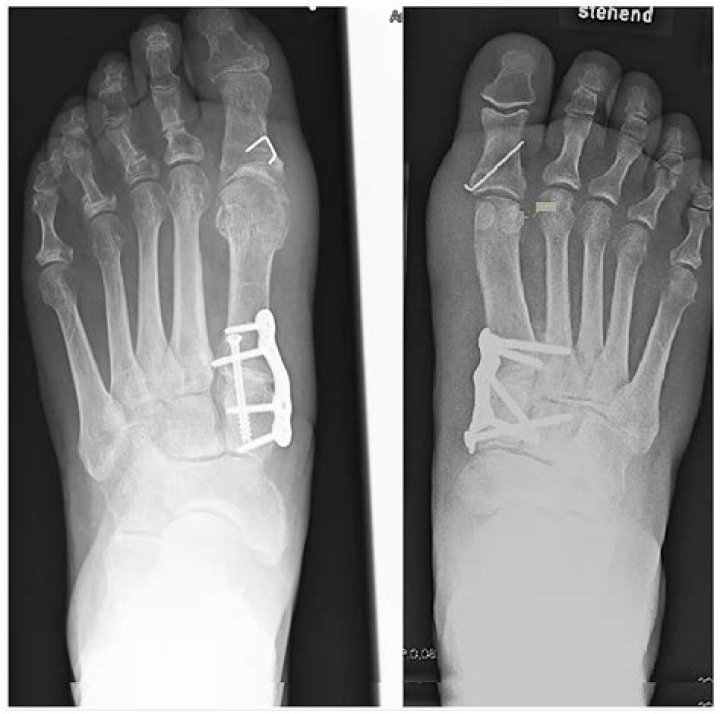

Tarsometatarsal (Lisfranc) joint arthrodesis using the Shark Screw® allograft

Tarsometatarsal joint fusion is a surgical procedure that fuses the bones of the middle foot and stiffens it to correct deformities in the tarsometatarsal region.

What is the third Tarsometatarsal joint?